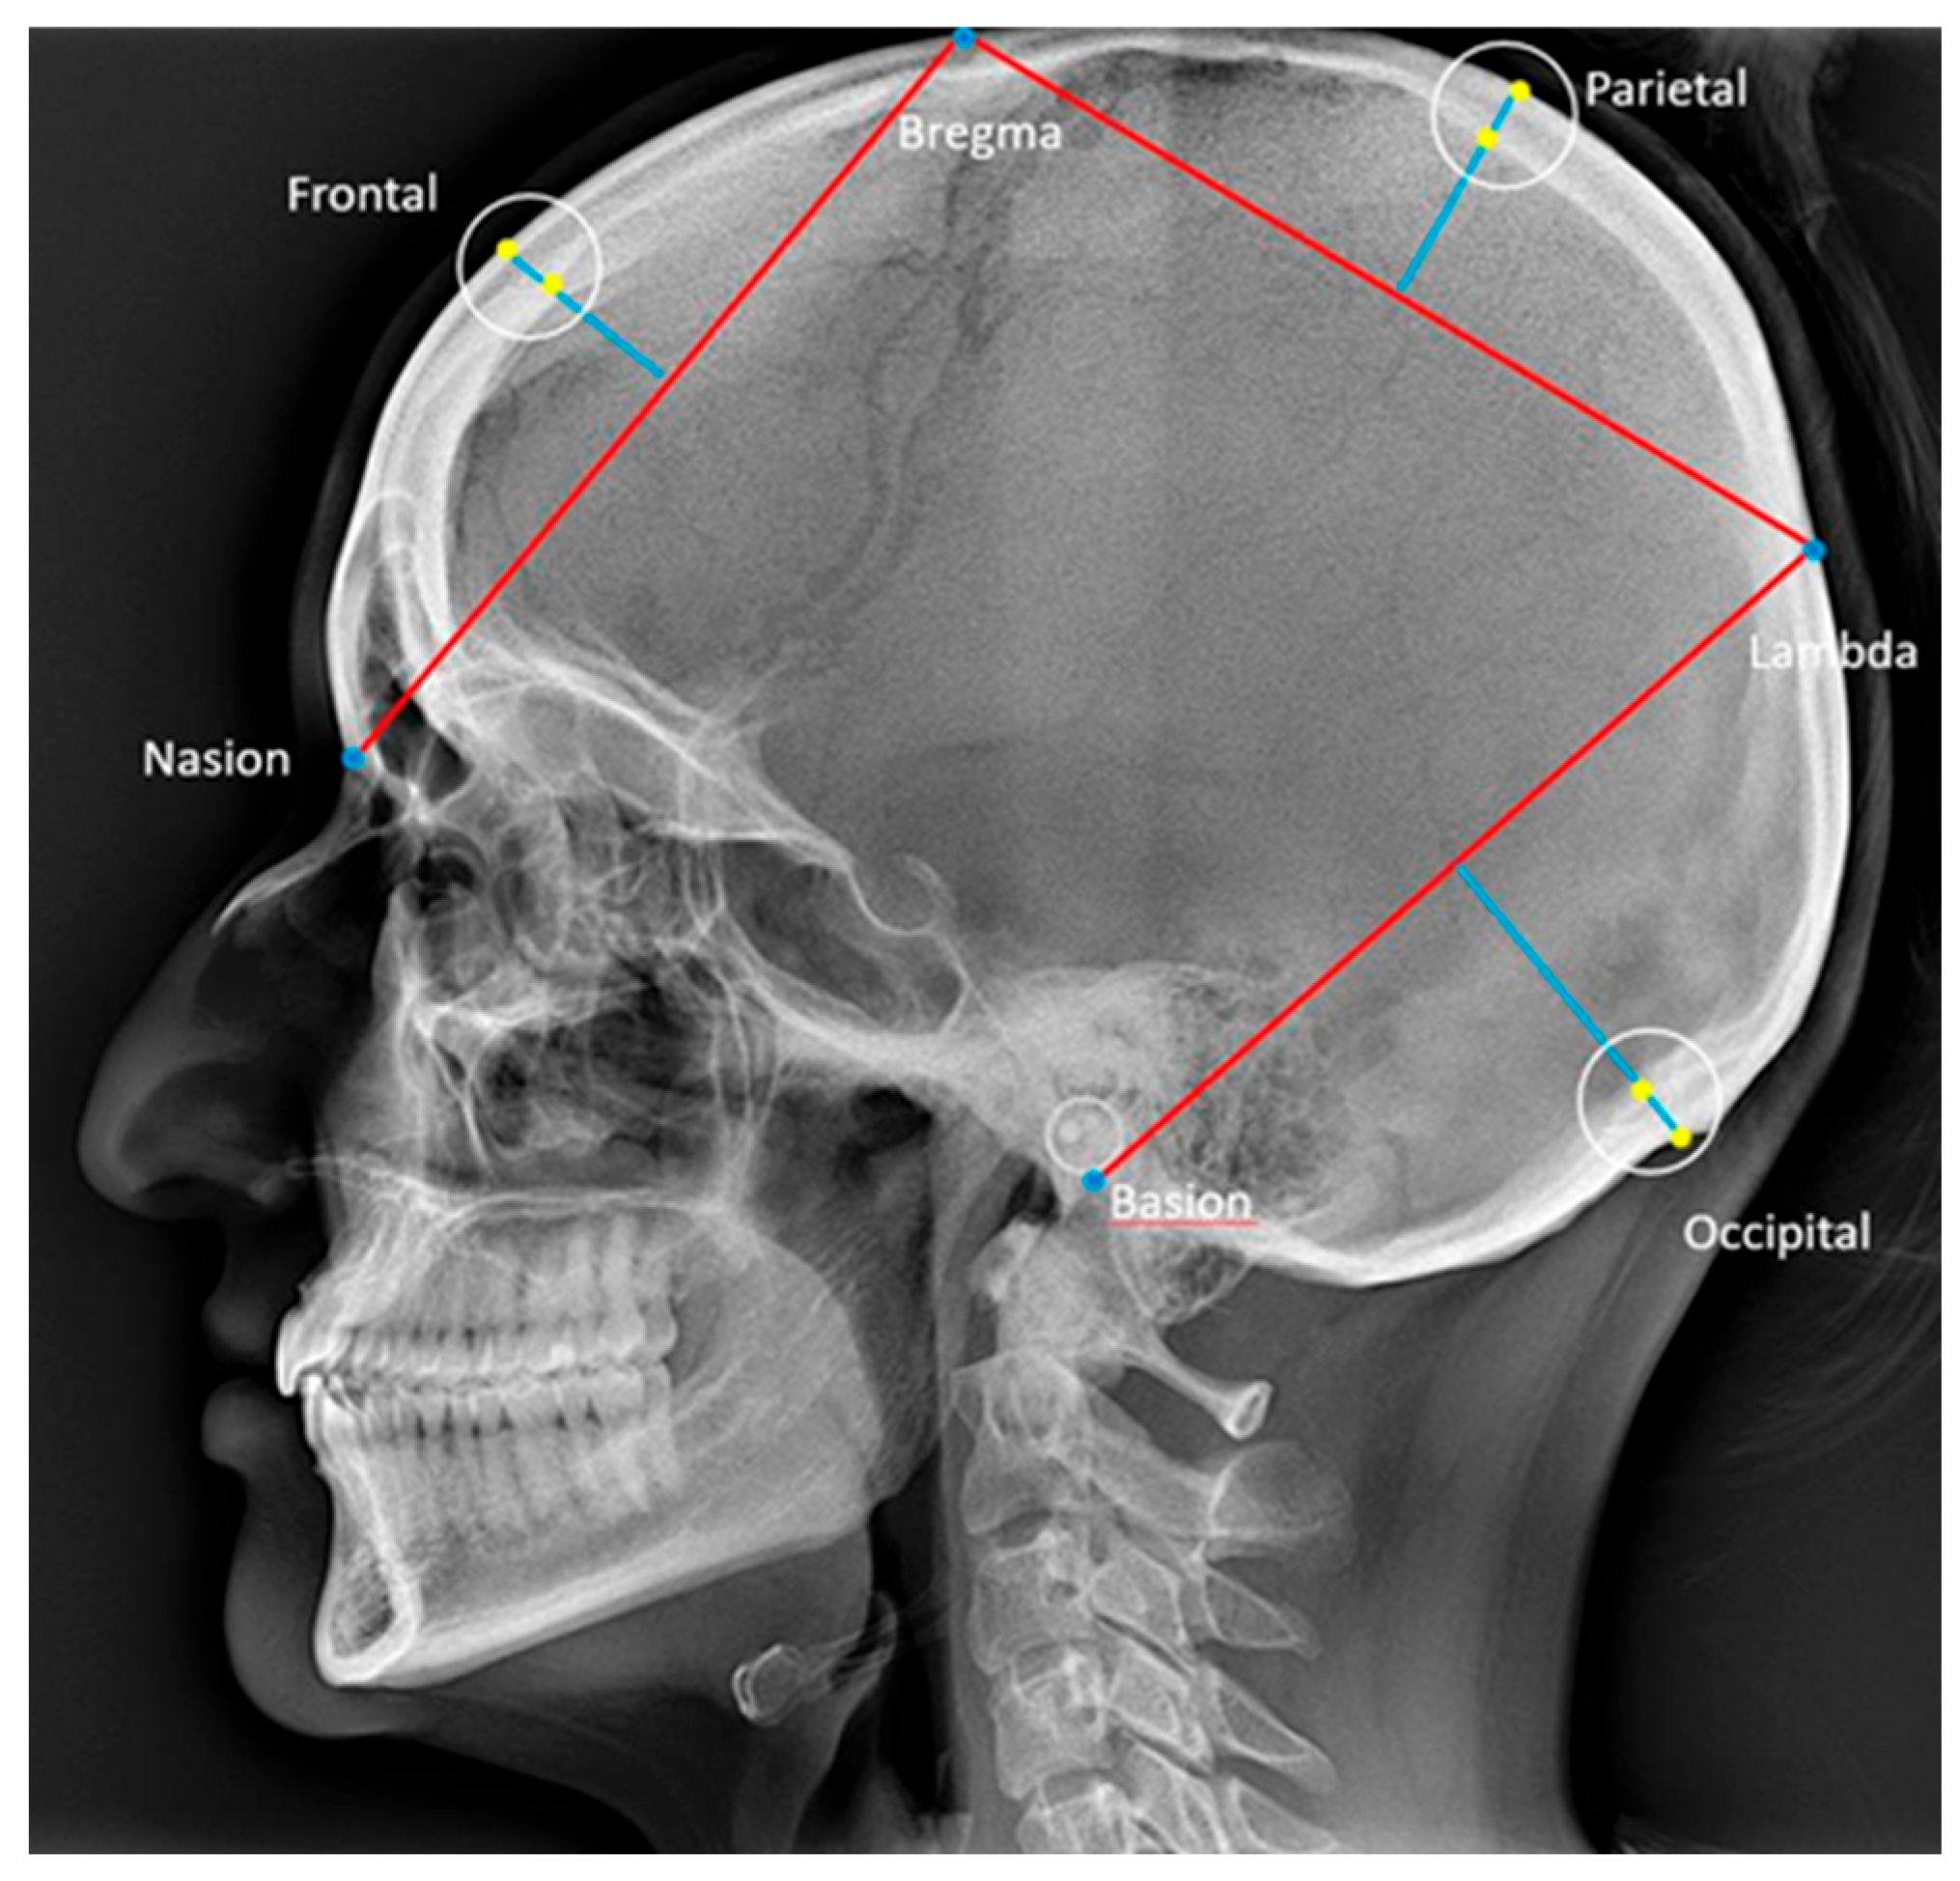

Skull thickness was measured frontally, parietally, and occipitally according to Axelsson [29], and the reference points and lines are described in Table 2 and illustrated in Figure 4 [29].

Figure 4.

Reference points and lines used for the description of skull thickness in the frontal, parietal, and occipital bones [29]. Nasion: the most anterior point on the fronto-nasal suture. Basion: the most posterior-inferior point on the clivus. Bregma: the intersection between the sagittal and coronal sutures on the surface of the cranial vault. Lambda: the intersection between the lambdoid and sagittal sutures on the surfaces of the cranial vault. The thickness of the frontal, parietal, and occipital bones were defined according to Axelsson et al. [29] as the distances from the points where the perpendicular bisectors of the cords nasion–bregma, bregma–lambda, and lambda–basion intersected the inner and outer contours of the respective bones.